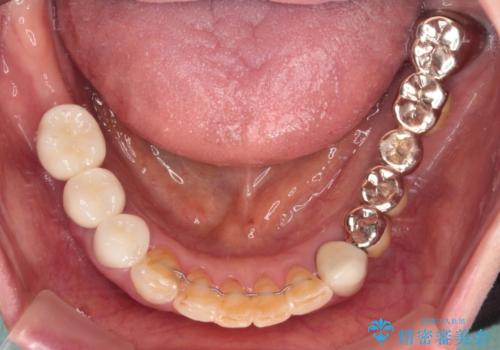

処置を予定していた歯を仮歯に変えた時点で、下顎前歯の部分矯正を行うかどうかを尋ねたところ、折角なので行いたいと言うことでしたので、矯正治療を行うこととしました。

インプラント埋入や根管治療治療など、治癒に一定の期間を要する処置の合間に矯正治療を行うことで、効率的に治療を進めて行くことができました。